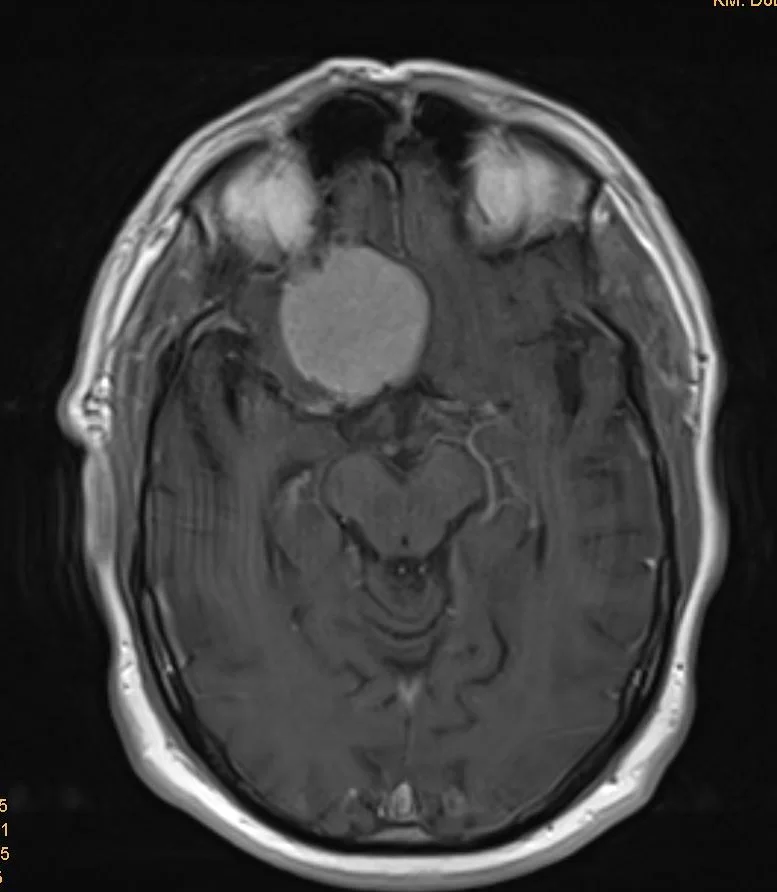

Ο απεικονιστικός έλεγχος με μαγνητική τομογραφία ανέδειξε χωροκατακτητική εξεργασία του προσθίου κρανιακού βόθρου, συμβατή με μηνιγγίωμα του φύματος του εφιππίου.

Προεγχειρητική Μαγνητική Τομογραφία Εγκεφάλου